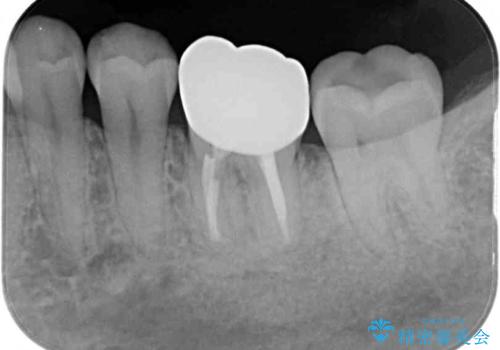

- 近医にてセラミックを装着した左下の奥歯に痛みが続いたとのことで来院された患者様です。

診査の結果、既に歯の神経は失活していたおり、排膿路が認められ、叩いたり触ったりしたときの痛みも確認されました。

根管治療を行った後にオールセラミッククラウンにて補綴することとしました。

初回の治療後には歯肉に認められた排膿の出口などの症状は消えていました。

補綴後6ヶ月経過しレントゲンを撮影したところ、遠心の歯根付近の病変が消失していることが確認できました。